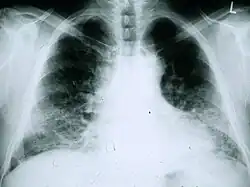

Radiología

Las radiografías de tórax resultan útiles para el seguimiento sistemático de los pacientes con FPI. Desafortunadamente, las radiografías de tórax estándar no ofrecen un diagnóstico, pero pueden revelar una reducción del volumen pulmonar, normalmente con marcas intersticiales reticulares prominentes cerca de las bases pulmonares.[1]